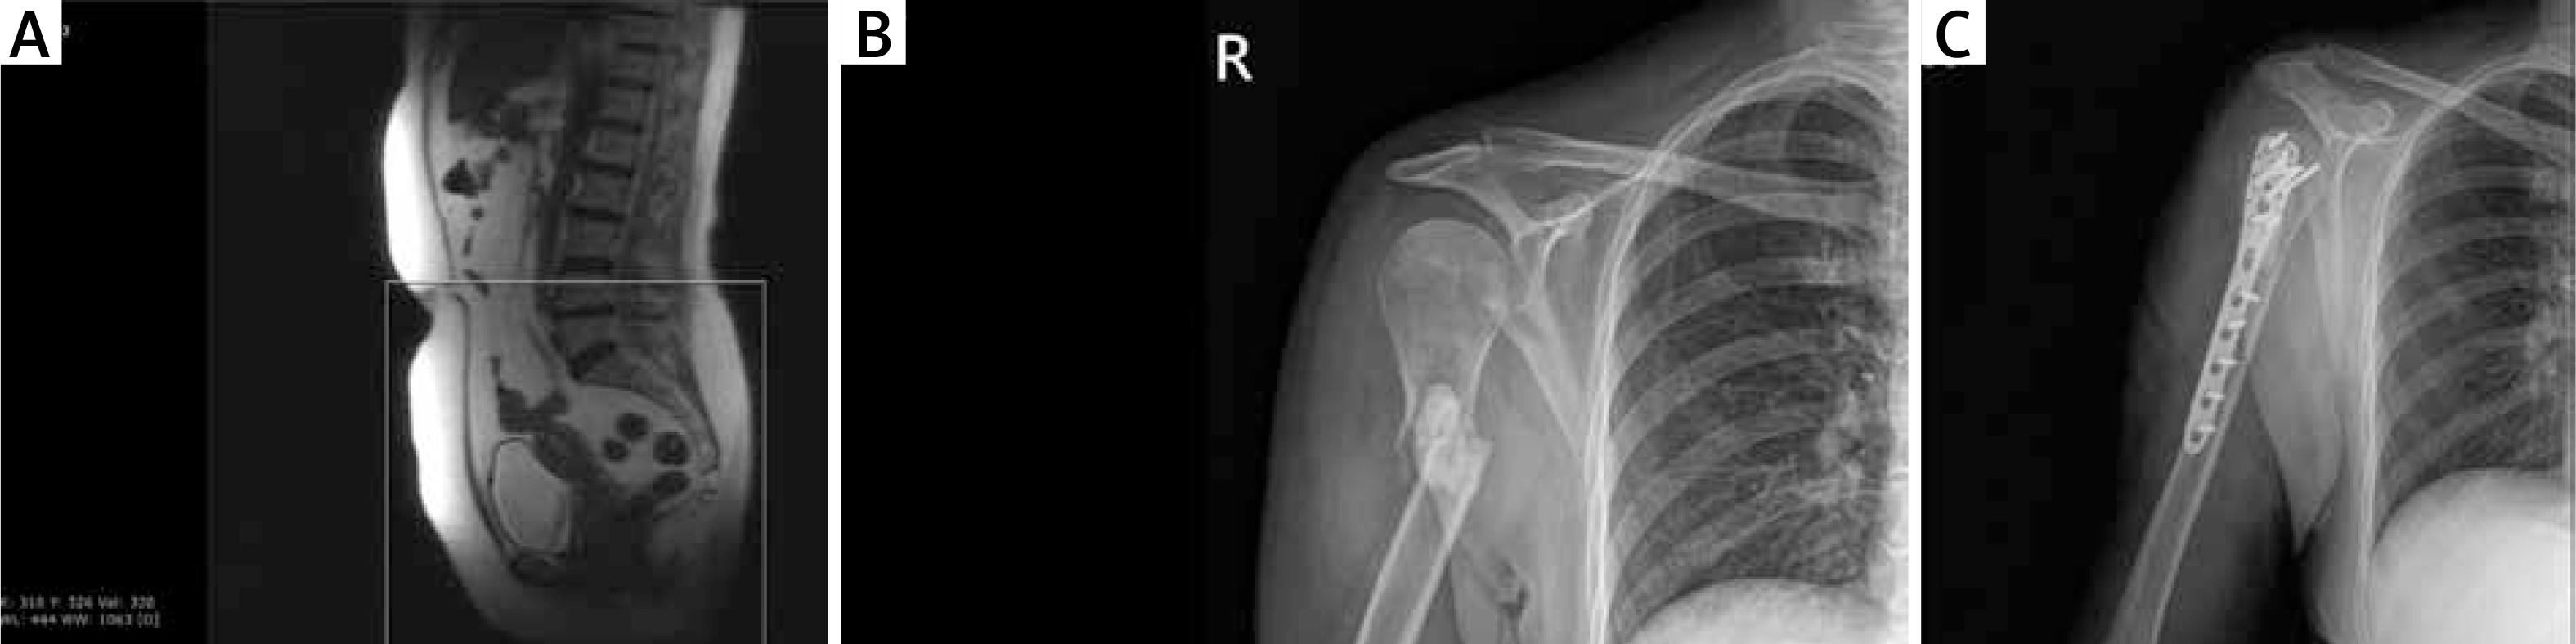

We present the case of a 58-year-old woman who sought dermatologic consultation in October 2023 due to multiple erythematous, firm, non-tender skin papules, plaques, and nodules of varying sizes, accompanied by shallow ulcers around a postoperative scar on her right upper arm (Figure 1 A). Upon clinical examination and a comprehensive review of her medical history, it was revealed that the patient had been admitted to the Gynaecologic Outpatient Department in February 2023 due to vaginal discharge and bleeding. Further examination detected tumorous tissue in the cervix, leading to a biopsy. Pathohistological analysis confirmed invasive squamous cell carcinoma. Pelvic magnetic resonance imaging (MRI) indicated Stage IIIC of cervical infiltration (Figure 2 A), and thoracic multi-slice computed tomography (MSCT) showed no evidence of tumorous dissemination but identified a solitary nodal change in the right lung lobe, likely a granuloma.

In June 2023, due to severe right shoulder pain, an MSCT was performed, revealing a 21 × 12 mm osteolytic zone at the humeral neck and a 15 × 8 mm zone at the posterior humeral neck contour, consistent with secondary deposits. Considering the atypical nature of cervical cancer metastases particularly to the humerus, a biopsy and pathohistological analysis of these changes were recommended. Consequently, the pathohistological evaluation of the proximal right humerus specimen confirmed joint metastases of squamous cell carcinoma. Additionally, in October 2023 the patient was hospitalized at the Orthopaedic Clinic due to a pathological fracture of the right humerus and the surgical intervention was performed (Figures 2 B, C). During her stay, livid nodules with shallow ulcerations around the postoperative scar were observed, prompting a consultation with a dermatologic oncologist. Dermatoscopic examination revealed signs consistent with cutaneous metastases, including a polymorphic vascular pattern, keratinization signs, central homogenous white zones, peripheral brown pigmented networks, and a polymorphic vascular pattern with arborized, linear, and comma-like blood vessels. Adjacent areas displayed structureless blue surfaces, bright white lines, and fields with brown pepper-like speckles (Figure 1 B). Based on these findings, the dermatologist-oncologist suspected cutaneous metastases and recommended a skin nodule biopsy for pathohistological analysis, which confirmed the presence of metastatic deposits on the skin proximal to the right humerus (epidermis is preserved; in dermis there is a cluster of atypical epithelial cells, pleomorphic nuclei, and visible mitoses with signs of keratinization) (Figures 1 C, D).